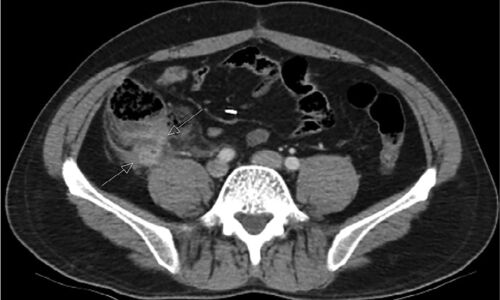

症例47:虫垂切除歴がある32歳男性に発症した右下腹部痛(Am J Emerg Med. 2020 Nov 9:S0735-6757(20)31019-6.)

病歴/身体所見 ・32歳男性 ・3年前に虫垂切除術既往あり ・2年前にstump appendicitisに対し残存虫垂切除術既往あり ・2日間持続する右下腹部痛と嘔吐のためER受診 ・McBurney点に手術痕を認める ・腸蠕動音は低下、右下腹部に圧痛と筋性防御と反跳痛を認め…